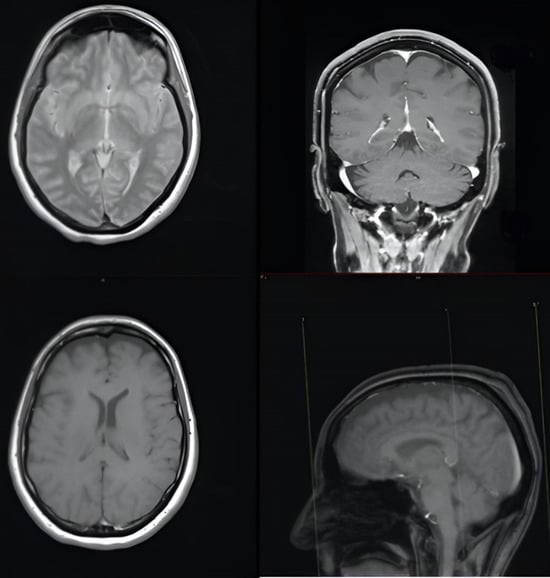

We report the case of a 47-year-old pre-menopausal Caucasian woman who presented to the Policlinico Umberto I hospital in Rome, with a 6-month history of subjective dizziness, oscillopsia, instability, imbalance, blurred vision, and photophobia, accompanied by severe vomiting, which resulted in severe weight loss (16 kg over 7 months) (Table 1). The medical history was significant for only hypothyroidism and her family history was positive for a sister with breast cancer. Clinical examination of our patient revealed marked fluctuations without prevalence to the side during Romberg and Fukuda tests, both with open and closed eyes. In video-oculoscopy (Supplementary Materials Video S1), the assessment of extraocular motility demonstrated isolated and intermittent episodes of low-amplitude, high-frequency horizontal saccades occurring without an intersaccadic interval, consistent with the clinical presentation of ocular flutter []. A comprehensive evaluation was performed, including contrast-enhanced brain Magnetic Resonance Imaging (MRI) (Figure 1), brain Computed Tomography (CT) scan (Figure 2), ophthalmological assessment, viral serology, autoimmune panel, complete blood count, and assessments of thyroid, renal, coagulation, hepatic function, vitamin D and B12 levels; all results were within normal limits. Paraneoplastic syndrome (ENS) sometimes precedes the diagnosis of cancer, necessitating a screening to detect an unidentified tumor. After excluding all other potential causes of the neurological symptomatology, a paraneoplastic origin was considered. Paraneoplastic autoantibody panels (anti-Ri, anti-Yo, anti-Hu, anti-CV2.1, anti-Amphiphysin, and anti-Ma2/Ta) resulted positive for anti-Ri onconeural antibodies with a value of 1:126 (51–256 strong positivity). A whole-body CT scan revealed multiple solid non-calcific nodules (at least 4 in the right breast QQEE), the largest measuring 13 × 9 mm, and right axillary lymphadenopathy measuring 24 mm (Figure 3). Mammography showed at least three nodular opacities with an irregular shape in the external superior quadrant of the right breast. The biggest ones were 13 mm (with intranodular microcalcifications) and 12 mm (BIRADS 5) (Figure 4). The breast ultrasound confirmed three solid irregular hypoechoic nodules measuring 11 mm, 9 mm, and 12 mm, as well as some right axillary lymphadenopathy, the largest measured 25 mm (Figure 5). Histological examination of an ultrasound-guided biopsy revealed invasive carcinoma “no special type” (NST) according to the 2019 World Health Organization (WHO) classification, with a grade 2 histology (G2) with occasional outbreaks of ductal carcinoma and axillary lymph node metastasis. Additionally, a bone scan revealed no evidence of the disease’s metastatic localization (Figure 6). A multidisciplinary team decided to proceed with a right mastectomy and a right axillary dissection. The final histopathological report showed an invasive multifocal NST grade 2 carcinoma, positive for ER (98%), PR (80%), Ki67 (32%) and negative for HER2 (Luminal B HER2 negative). The resection margins were free of neoplastic infiltration. Two of the 14 lymph nodes were positive for invasive carcinoma. The final staging was G2 pTle pNla (2/14) MO, stage IIA. The patient received hormone therapy (Exemestane 25 mg daily and Decapeptyl 3.75 mg daily) due to high hormone receptor expression. Surgical treatment of the primary tumor did not improve neurological symptoms, prompting the patient to undergo intravenous steroid therapy; however, this also did not lead to any clinical improvement. The patient was evaluated at 2, 6, 12 and 24 months with clinical, radiological and serological examinations. On vestibular examination 2 months post-surgery, subjective dizziness and instability persisted. On video-oculoscopy, the patient presented ocular flutter with intermittent horizontal saccades especially in the lateral gaze. Total body CT scan (Figure 7) and breast ultrasound (Figure 8) at 2 months were negative for neoplastic recurrence or metastases. Serology for anti-Ri antibodies remained positive. Six months after surgery, the patient, who had been on Prednisone 50 mg/day, was admitted to the neurology department of another hospital. Patient reported an improvement in headache and a reduction in the frequency of emesis, but no improvement of the ocular and vestibular symptoms. The neurological examination documented oculovestibular syndrome with ocular flutter that was not inhibited by fixation, forcing the patient to keep her eyes closed, ataxia, head and trunk tremor, hypomimic facies, hypertonia in the right upper limb with difficulty in movements of the right hand, difficulty getting up from the chair without support, instability in open and closed eyed Romberg test, moon facies due to iatrogenic Cushing’s, slow, diprosodic and hypophonic speech. During admission, an MRI of the brain and brainstem was performed, which showed a slight enlargement of the peri-brain spaces in the frontal area and of the peri-brain spaces in the cerebellar area, possibly indicative of initial atrophy. Blood tests confirmed the presence of anti-Ri antibodies. Considering the immune-mediated genesis of the paraneoplastic syndrome, the patient underwent five sessions of plasmapheresis followed by a course of intravenous immunoglobulin (0.4 g/kg/day) with a slight and temporary clinical improvement. Due to the presence of a mild right rigid-kinetic hemi-syndromes with associated hypomimia and hypophonia, a genetic study for Parkinson’s disease was conducted and L-DOPA therapy was prescribed, which was then discontinued as the patient reported worsening symptoms. The patient underwent brain SPECT with receptor tracer to evaluate the presynaptic dopaminergic system the basal ganglia, which showed no impairment of the nigrostriatal presynaptic dopaminergic system. Due to the lack of response to chronic steroid therapy and the development of clinical signs of iatrogenic Cushing’s, following endocrinological consultation, the dosage of Prednisone was progressively reduced and then replaced by Cortone Acetate. Bone mineral density was normal. After one month, the patient was transferred to a rehabilitation center to undergo neuromotor and vestibular rehabilitation until the patient was transferred back to the prior neurology department due to a clinical worsening, in particular of the eye complaints. The patient was unable to perform more than a few steps without support, showed multidirectional fluctuations on the Romberg test with trunk instability. At eye opening there was persistence of the ocular flutter, with mydriatic pupils (left > right) and a cloudy but present response to direct light stimulus. The other cranial nerves were intact. Thermal tactile and pain sensitivity were preserved. Osteotendinous reflexes were brisk and symmetrical in the upper limbs and hypotensive in the lower limbs. Coordination tests (index-nose, index-index, finger-tapping), revealed mild motor impairment on the right side with kinetic and postural tremor and fine tremors in the upper limbs. During hospitalization, the patient underwent a new course of plasmapheresis (four sessions in 8 days) combined with intravenous immunoglobulins (0.4 g/kg/day for 4 days) with slight clinical benefit. Due to the need for chronic immunosuppressive treatment, oral therapy with Azathioprine at an initial dosage of 25 mg/day, later increased to 50 mg, was administered. A contrast-enhanced MRI of the brain and cervical spine was performed, which showed essentially unchanged findings compared to the previous check-up, including a modest enlargement of the peri-brain spaces in the frontal area and peri-foliar spaces in the cerebellum, expressing initial signs of atrophy. Slight clinical improvement was documented during hospitalization, particularly in head tremor and ocular flutter, allowing the patient to fixate, despite the persistence of pathological eye movements. Gait was improved, although the patient remained ataxic. In view of this progress, the patient was again transferred to the neuromotor rehabilitation center for one month at the 12 months follow-up visit, the patient reported a worsening of the oculovestibular syndrome with inexhaustible flutter preventing fixation, worsening of rigidity in the right upper limb and occasional dysphagia. The neurological examination showed dystonic flexion in the right upper limb and plastic hypertonia in the upper limbs bilaterally (right > left), but no hypertonia in the lower limbs. Independent ambulation was not possible. The patient had an intravenous infusion of cyclophosphamide, which brought only slight and transient improvements in symptoms. After 24 months from the surgery, the patient was re-evaluated in our hospital, and a vestibular examination via oculoscopy confirmed the presence of the flutter with horizontal saccades, which were slightly reduced compared to the first assessment in 2022. Vestibulospinal tests revealed a severe postural deficit, with ataxic walking and right upper limb rigidity.

Figure 4. Three nodular opacities with an irregular shape and intranodular microcalcifications at the level of the right QSE showed by mammography.